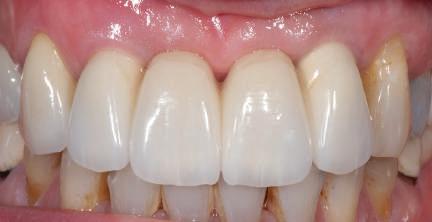

Prin urmare marginea restaurării se poate plasa în mod predictibil subgingival la nu mai mult de 1,5mm sub marginea gingivală. De fapt, în cazul unui bont de titan sau metal, profunzimile marginale de 0,5mm lingual, 1mm mezial şi distal şi 1,5mm pe vestibular ar trebui să asigure acces adecvat la margini pentru curăţarea cimentului şi a ascunde joncţiunea dintre bont şi restaurare (fig. 8).

Figurile 8. Cu ajutorul unui model de ţesut moale şi al unei sonde parodontale, se poate localiza cu precizie profunzimea marginii bontului. 9, 10. Materialul pentru ţesutul moale reprezentat pe model permite adaptarea contururilor subgingivale ale bontului la conturul ideal (fig. 9), şi când se îndepărtează, oferă acces la interfaţa analogului (fig. 10).